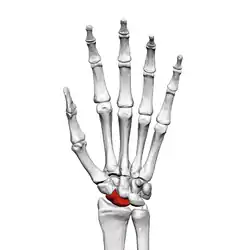

Left hand anterior view (palmar view). Scaphoid bone shown in red.

The scaphoid bone is one of the carpal bones of the wrist. It is situated between the hand and forearm on the thumb side of the wrist (also called the lateral or radial side). It forms the radial border of the carpal tunnel. The scaphoid bone is the largest bone of the proximal row of wrist bones, its long axis being from above downward, lateralward, and forward. It is approximately the size and shape of a medium cashew nut.

The scaphoid is situated between the proximal and distal rows of carpal bones. It is located on the radial side of the wrist,[1]:176 adjacent to the styloid process of the radius.[2] It articulates with the radius, lunate, trapezoid, trapezium, and capitate.[1]:176 Over 80% of the bone is covered in articular cartilage.[3]